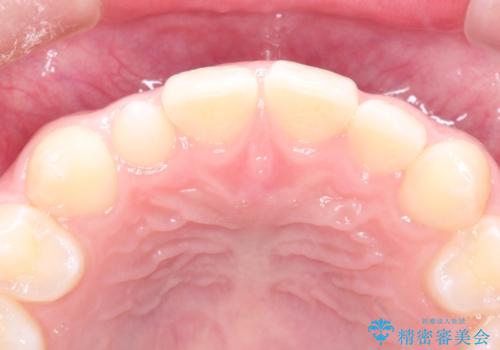

- 上の歯の隙間が気になるとのことで来院されました。

上顎の正中に隙間があり、右上の2番目の歯が通常の歯より小さい矮小歯でした。

正中の隙間をインビザライン矯正で閉鎖して、右上の2番目の歯にはセラミックを装着する計画としました。